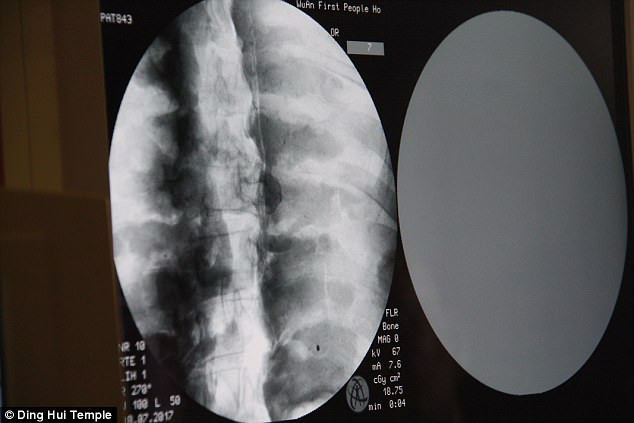

(Kiến Thức) - Các chuyên gia vô cùng bất ngờ khi tiến hành chụp cắt lớp vi tính xác ướp của vị đại sư Phật giáo sống cách đây 1.000 năm. Kết quả kiểm tra cho thấy bộ xương và sọ não của xác ướp còn nguyên vẹn một cách đáng kinh ngạc.

Các chuyên gia tiến hành chụp cắt lớp vi tính xác ướp đại sư Từ Hiền trước sự chứng kiến của các nhà sư, phật tử và phương tiện truyền thông.

Những người có mặt tại sự kiện trên đều vô cùng bất ngờ khi các chuyên gia thông báo thi hài đại sư Từ Hiền vẫn còn đầy đủ xương và sọ não hoàn chỉnh.

"Chúng ta có thể trông thấy xương cốt đại sư vẫn còn chắc khỏe như xương của người thường", bác sĩ Wu Yongqing chia sẻ.

Theo bác sĩ Wu Yongqing, xương hàm trên, hàm dưới, xương sườn, cột sống và tất cả khớp đều hoàn chỉnh. Điều này thật đáng kinh ngạc.